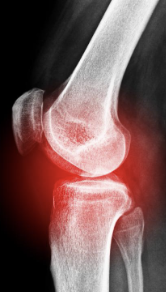

무릎 관절염 증상 원인 치료방법 총 정리 알아보아요 무릎 관절염 증상 원인 치료방법 등 무릎 관절염과 관련된 정보를 알아보도록 하겠습니다. 무릎 관절염은 무릎 관절의 연골 파괴, 염증 및 변형으로 인해 발생하는 질환입니다. 증상으로는 통증, 감각 이상, 충동성 통증, 강직성 및 관절의 이상운동이 포함된다. 주요 위험 인자로는 노화, 비만, 골관절염, 부상 및 과도한 사용 등이 있습니다. 진단은 증상 및 영상진단 검사를 통해 이루어지며, 치료는 수술, 약물 치료, 생활습관 변화, 물리 치료 등이 있습니다. 무릎 관절염은 진행성이며, 조기 발견 및 치료가 중요합니다. 예방을 위해서는 체중 조절, 적극적인 운동, 관절 보호를 위한 적절한 신발 착용 등이 필요합니다.